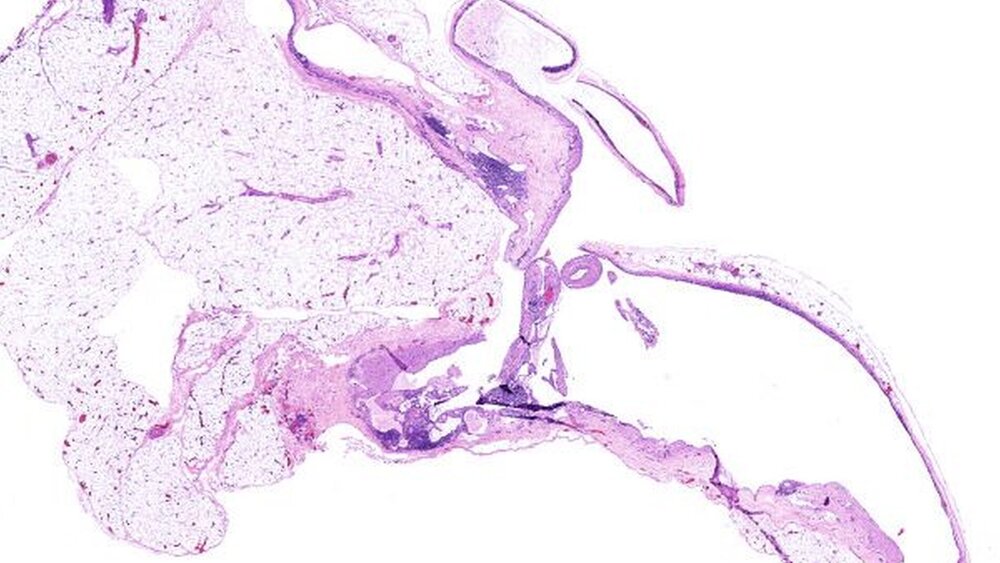

Es erfolgte die operative Exstirpation des Lymphangioms inklusive eines 2 cm langen zuführenden Lymphgefäßstils aus dem umgebenden Bindegewebe (Abbildungen 4 a und b). In der endgültigen histologischen Untersuchung zeigten sich in reifem Fett-gewebe zystisch erweiterte Lymphgefäße, ausgekleidet durch zartes Endothel. Intraluminal wurden eiweißreiche Flüssigkeit, vereinzelte Siderophagen und korpuskuläre Blutbestandteile beschrieben (Abbildung 5). Der Befund war ebenfalls vereinbar mit einem Lymphangiom.